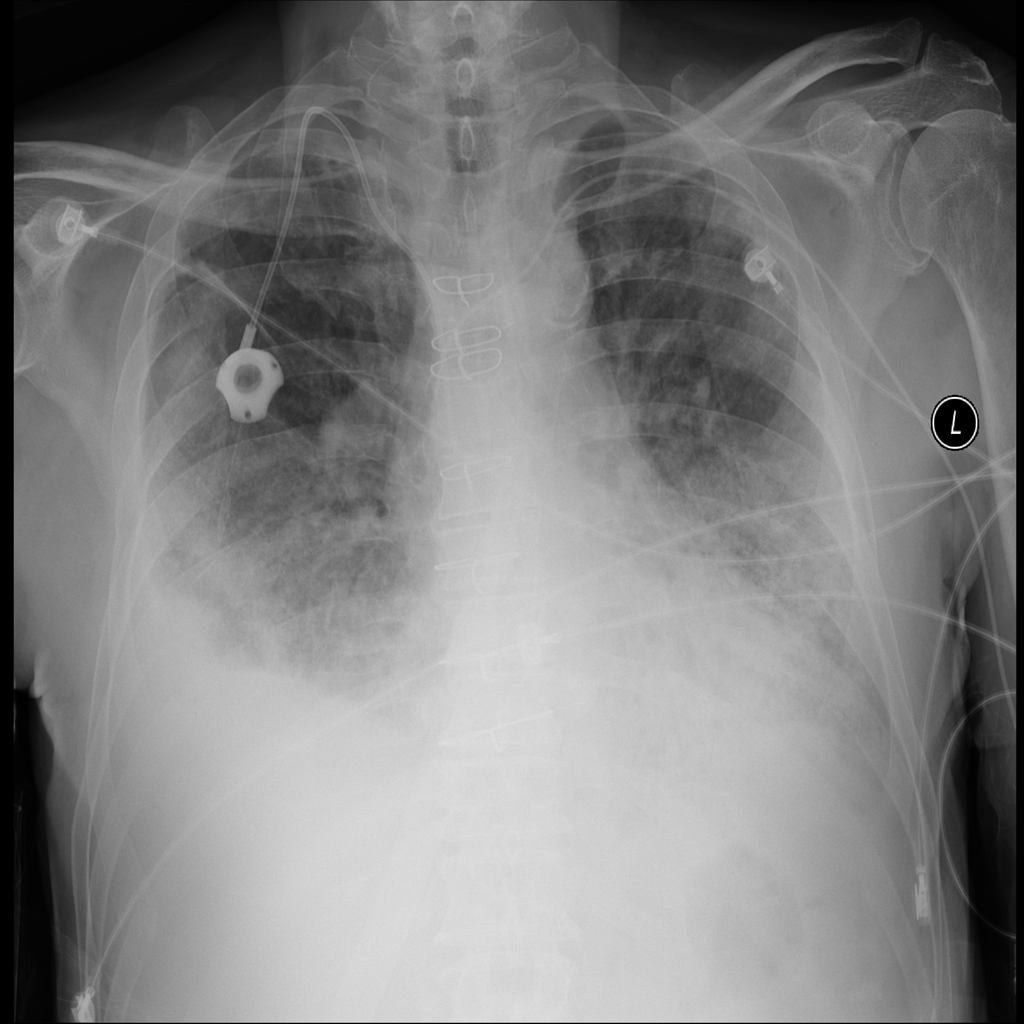

PAT-C0E5 · IMG-015Pneumonia

PAT-C0E5 · IMG-015

AP